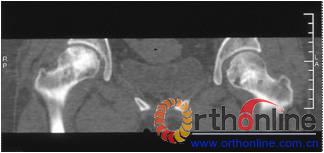

病灶修复情况比较,加用BMP2组病灶修复的完全性及硬化骨数量普遍优于未加BMP2组。(图3)

图3-1 女,31岁,SARS患者骨坏死,(1)MRI示双侧股骨头坏死,右Ⅱb(B型),左Ⅱc(C1型);(2)打压植骨术(未加BMP2)后坏死修复不完全,仍遗留股骨头软骨下病灶未完全修复, 5年随访关节功能优(Harris评分96分)

图3-2 女,30岁,SARS患者骨坏死,(1)术前MRI示双侧骨坏死;右Ⅱc期C3型,左Ⅱb期B型,打压植骨术(加BMP2),(2)5年后CT显示病灶修复好,关节功能优